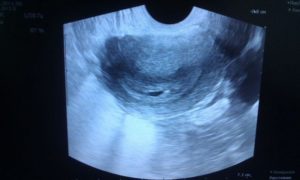

На каком сроке можно более-менее точно определить беременность по УЗИ? Если у врача, который проводит диагностику высокая квалификация и ультразвук имеет расширение высокого качества, то вполне вероятно зародыш можно увидеть размером от 3 до 5 миллиметров в диаметре. Это значит, что можно определить беременность уже через несколько дней после задержки. С какого срока тогда УЗИ показывает беременность после зачатия? Эта цифра будет составлять ровно 21 день.

Но намного эффективнее делать УЗИ на 10 день задержки. Процедура в этом случае проводится при помощи вагинального датчика.

Но не следует надеяться, что УЗИ покажет полностью точный результат. Даже если специалистом было выявлено плодное яйцо, то это никак не означает, что зачатие случилось. Яйцо может оказаться пустым и не иметь внутри себя эмбриона.

На ранних сроках беременности можно различить такие признаки:

- можно увидеть круглое или овальное образование;

- диаметр образования будет составлять около 4-5 миллиметров;

- вокруг него можно увидеть тонкую оболочку;

- во время маточной беременности плод будет находиться в углу матки;

- внематочная беременность характерна наличием эмбриона в маточной трубе или даже в брюшной полости.